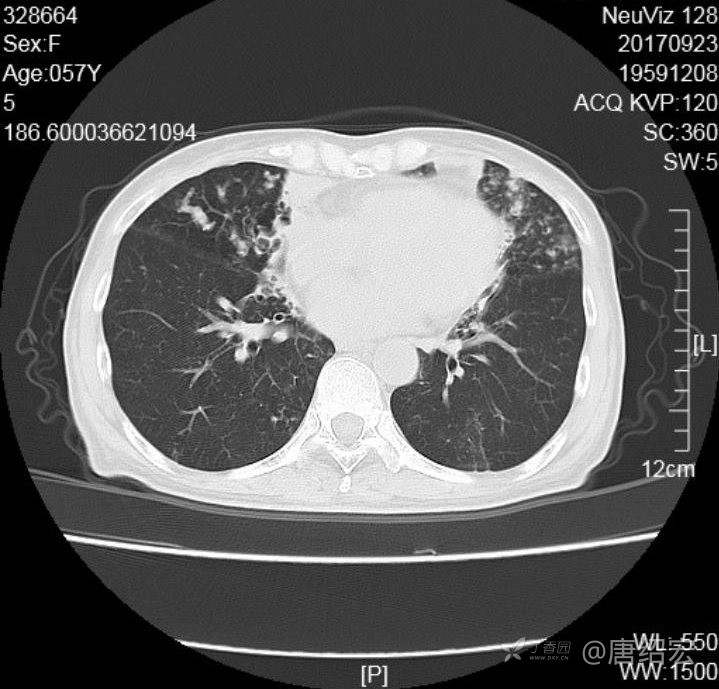

中年女性满肺树芽征还有支气管扩张,考虑什么疾病?

女,57岁,

主诉:发热、咳嗽、咯黄痰,胸闷3天入院。